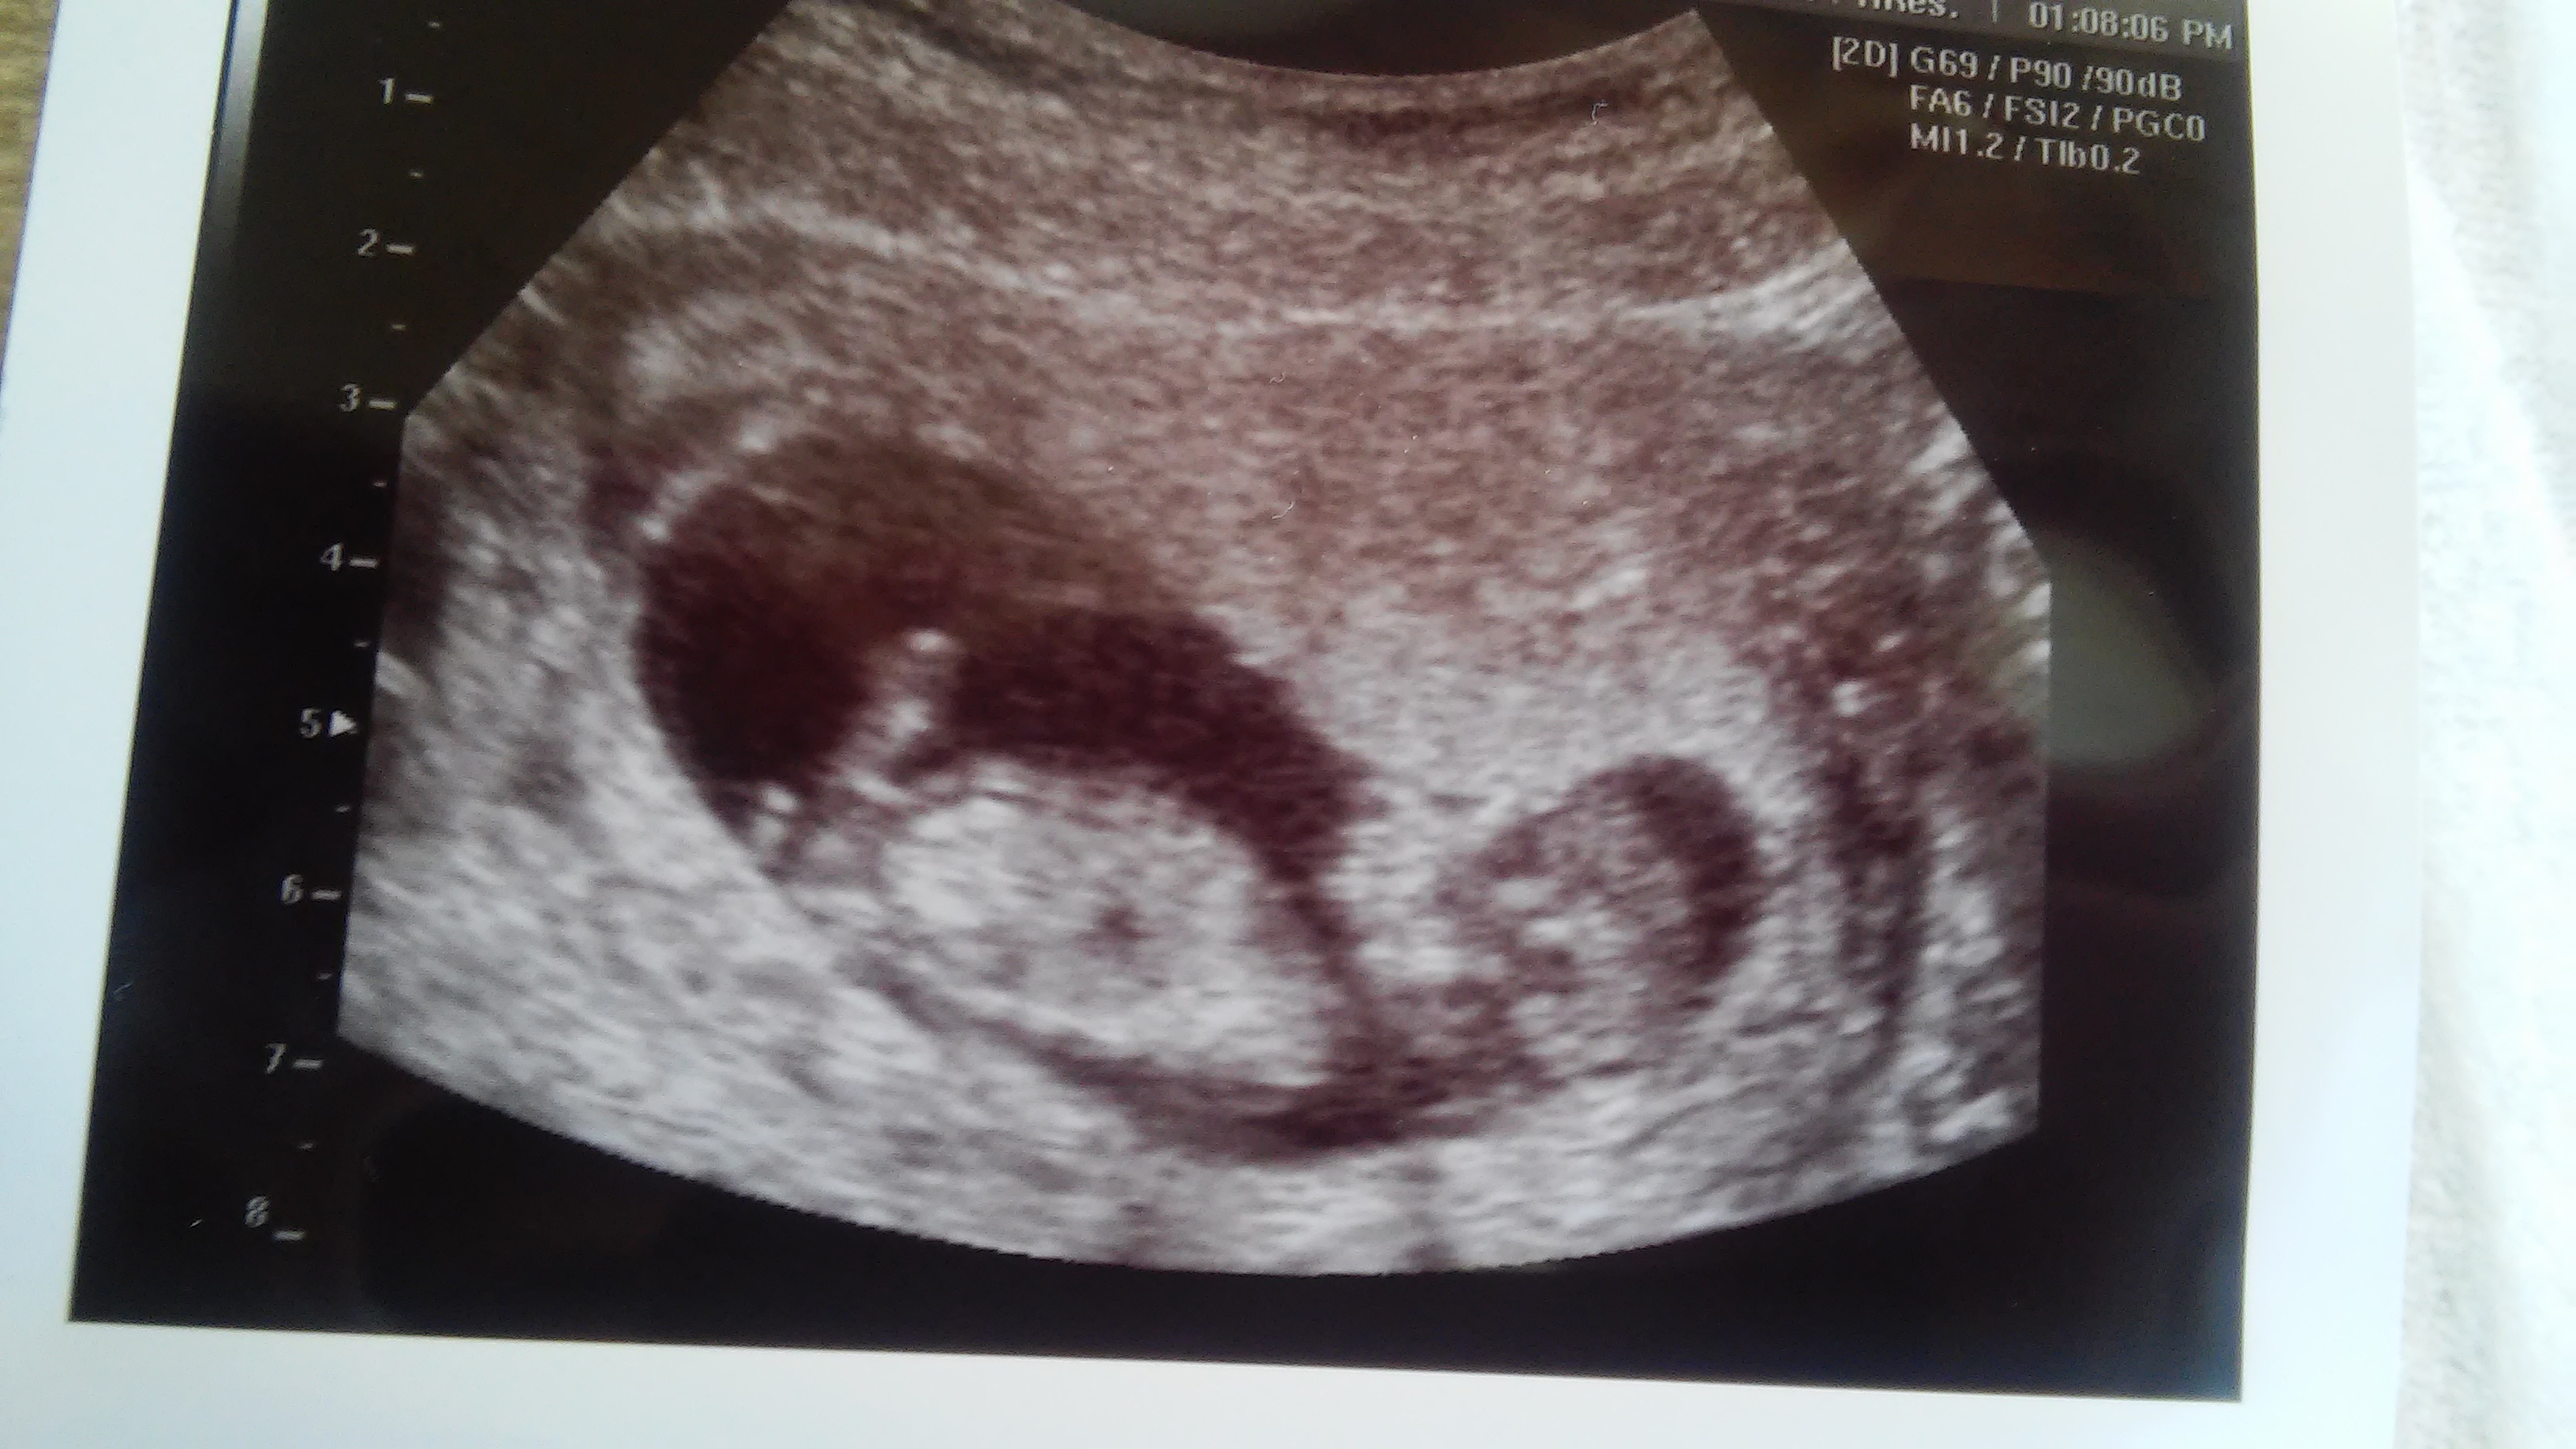

PLEASE help guessing gender.. boy or girl??? 12wks

Im am dying to know what i will have a boy or a girl! im 12 weeks and 2 days and had an ultrasound done today. PLEASE NOTE the umbilical cord was basically in the way the whole time thats the huge white thing in between the legs lol, so dont mistake that for something else :-)im hoping someone is able to look past the cord!! the ultra sound lady did gave me a picture of the butt, she placed an arrow next to it. they didnt want to give me a guess on the gender because theyre not allowed to with 12 weeks...

please help me figuring this out!! thank you so much!!Attachment 25235 Attachment 25236 Attachment 25237